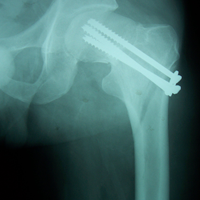

Case:7 Fracture Neck Femur with Implant failure and Re-Fixation with hemi-arthroplasty

Alcoholic Gardener by profession had slipped in bathroom & fell. He sustained fracture neck femur.He was operated with closed reduction & CC Screw fixation under IITV. Two weeks’ post fixation he again fell & sustained fracture in sub trochanteric region. He was treated with Hem-Arthroplasty with Tension band wiring.

Pre-Op

Post-Op